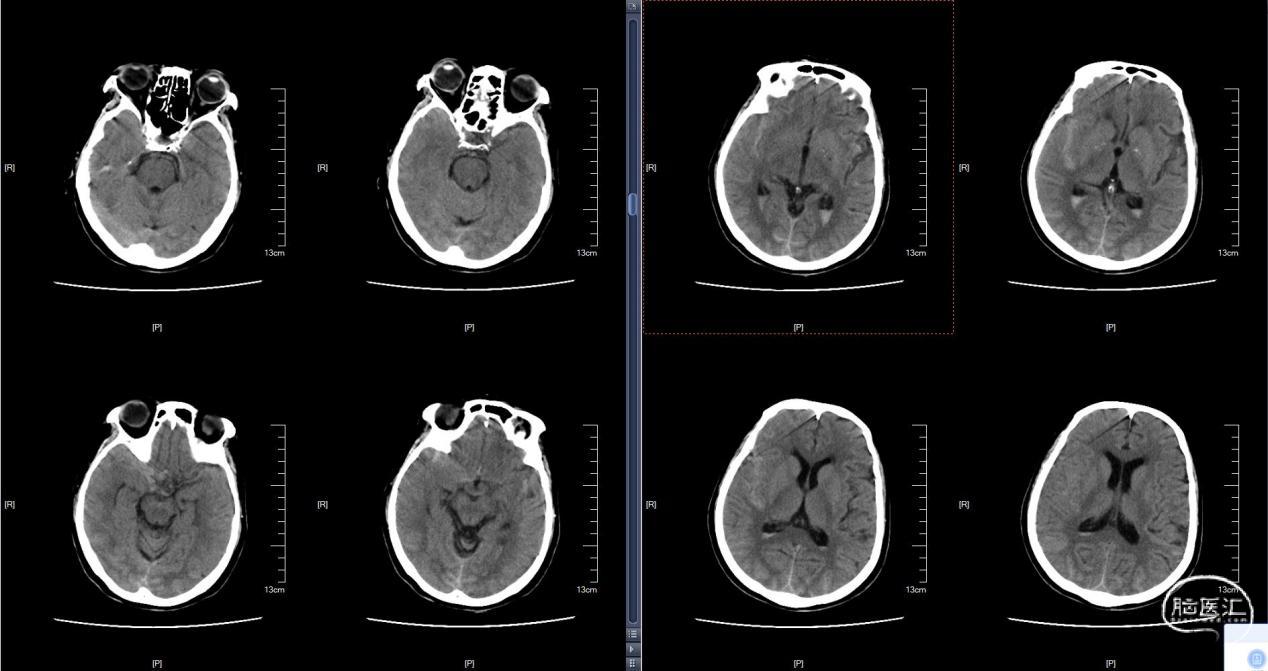

颅脑CT:蛛网膜下腔出血。

入院后行DSA检查,显示右侧颈内C6-7段动脉瘤右侧大脑中动脉M1分叉动脉瘤。

C6-7段动脉瘤位于颈内动脉上壁,指向内上方,考虑血泡样动脉瘤,结合蛛血位置,及动脉瘤形态、大小,考虑颈内动脉血泡为责任动脉瘤。